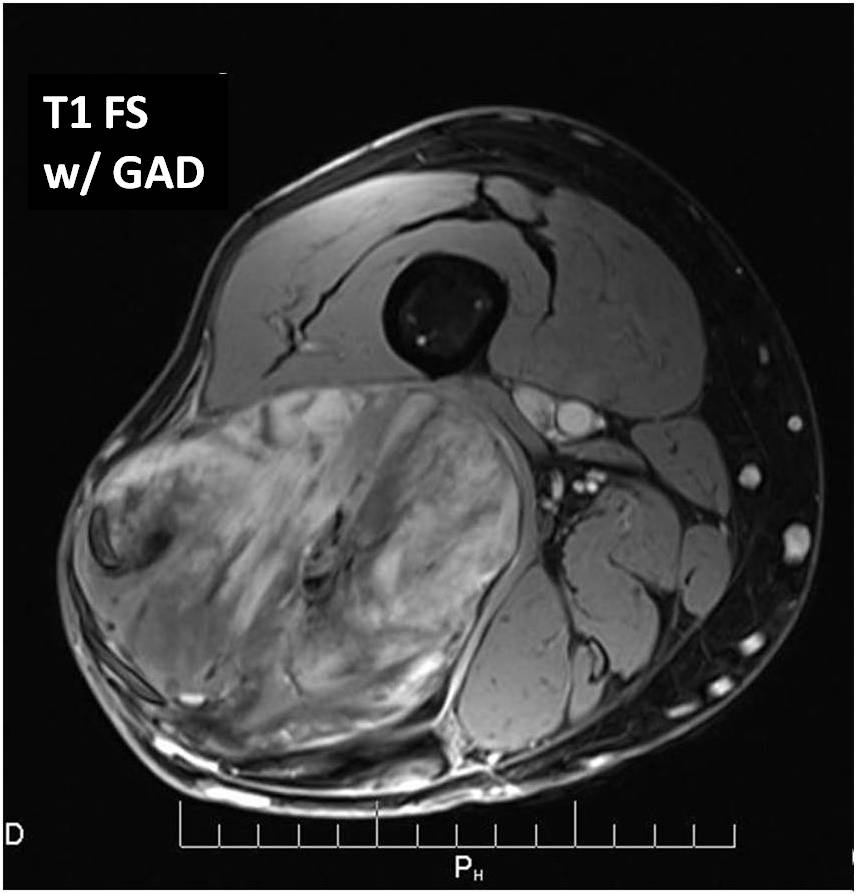

MRI (Fig. 2 and 3)

• Large well defined multilobulated mass.

• Low signal on T1 weighted images. Usually adipose tissue composes less than 10 percent of the tumor and is difficult to detect on an MRI as high signal on T1W images. (Fig. 2A)

• Marked high signal on T2 weighted sequence. (may mimic a synovial cyst) (Fig. 2B) The myxoid/mucinous tissue consists of mucopolysaccharides that holds onto water and shows up high signal on T2W images.

• Identification of the subtle fat requires comparison of T1W and T2W images in the same plane but is usually very difficult to discern. (Fig. 2)

Fig 2. T1-weighted MR image (A) of a myxoid liposarcoma demonstrates well-defined mass of intermediate signal intensity with central areas of high intensity. T2 –weighted fat-suppressed image (B) heterogeneously mostly high signal intensity within the lesion.